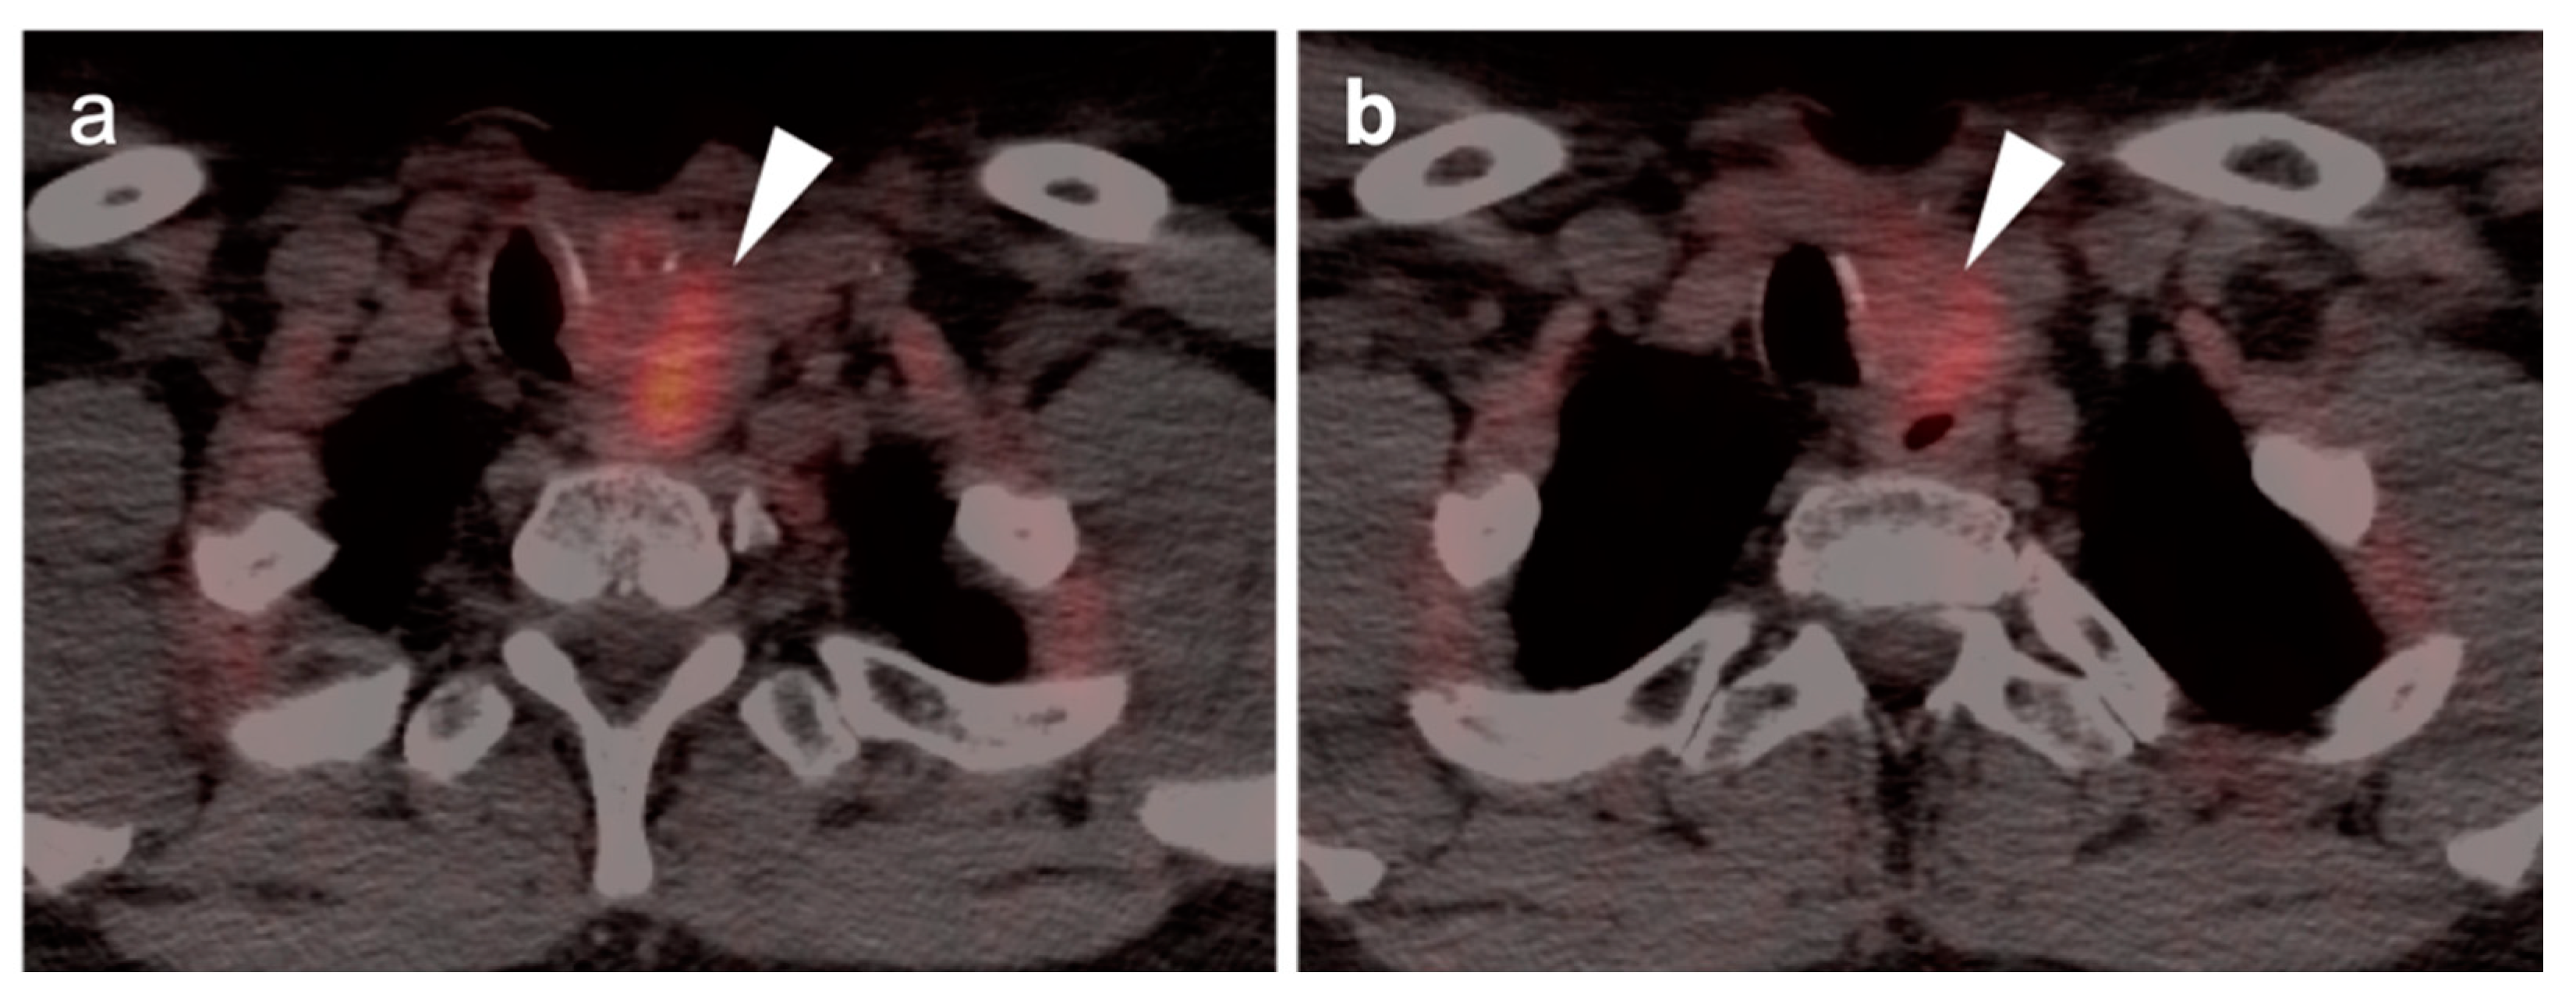

2.6. Thyroid Cancer

- Differentiated thyroid cancer

- Medullary thyroid cancer